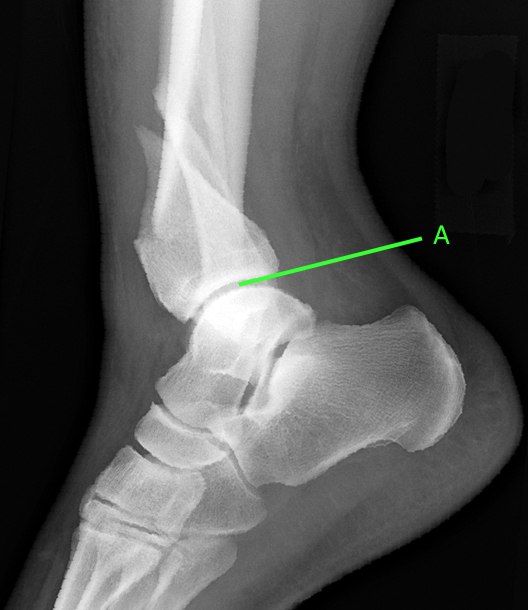

СКЛАДНИЙ СУГЛОБ (ЯК ВИЛКА). Є ВСІ ПЕРЕДУМОВИ ДЛЯ РОЗТЯГНЕННЯ ЗВ'ЯЗОК І ЗМІЩЕННЯ КІСТОК. РОЗПІЗНАЙТЕ СУГЛОБ.

варіанти відповідей

СУГЛОБ УТВОРЕНИЙ СУГЛОБОВИМИ ПОВЕРХНЯМИ ЛАТЕРАЛЬНОЇ І МЕДІАЛЬНОЇ КІСТОЧКИ ТА ТІЛОМ ТАРАННОЇ КІСТКИ. РУХИ НАВКОЛО ФРОНТАЛЬНОЇ ОСІ. ЧАСТО - РОЗТЯЖІННЯ, ВИВИХИ, РОЗРИВИ, ПЕРЕЛОМИ. РОЗПІЗНАЙТЕ СУГЛОБ.

КОЛІННИЙ С.

ГОМІЛКОВО-СТОПНИЙ С.

КУЛЬШОВИЙ С.

ЛІКТЬОВИЙ С.

ПЛЕЧОВИЙ С.

ПРОМЕНЕВО-ЗАП'ЯСТКОВИЙ С.